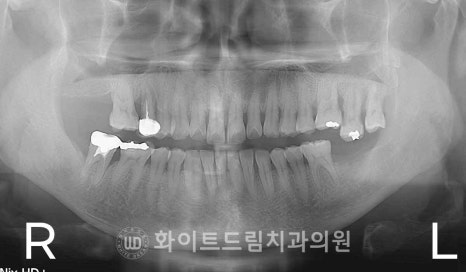

[동일 인물이며 동일 환경에서 촬영됨 / 강남역치과 임플란트 총 치료 기간 : 16.12.28 - 17.07.08]

수술 시점은 좌우가 서로 달랐지만,

최종 보철은 교합 균형을 보다 정확하고 안정적으로 맞추기 위해

양쪽 임플란트의 장착 일자를 의도적으로 동일하게 맞추어 진행했습니다.

어금니 보철은 한쪽씩 따로 장착하면

교합 높이, 중심 접촉, 저작력 분배가 미세하게 어긋날 수 있기 때문에

가능하면 양측을 같은 날 세팅하는 것이 가장 이상적이랍니다.

그래서 이번 환자분도

두 부위의 치료 타이밍 차이가 있었음에도

보철은 7월에 양측 동시 세팅으로 마무리를 하게 되었죠.